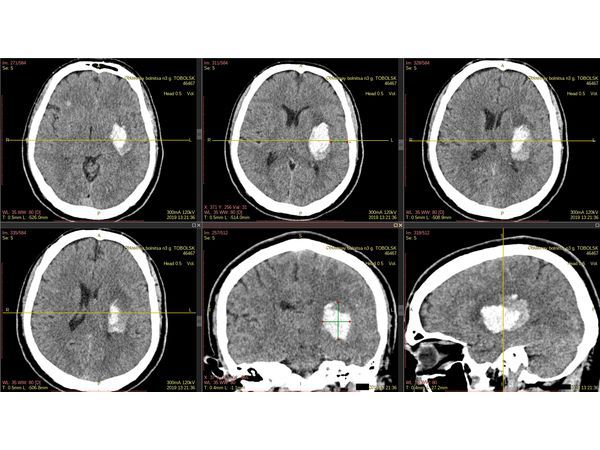

На КТ головного мозга в левой путаменально-капсулярной области выявлена инсульт-гематома.

С помощью бесплатной версии программы RadiAnt DICOM Viewer выполнена предоперационная разметка, т.е. намечен план операции.